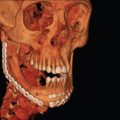

When considering the anatomy of dentoalveolar injuries, distinction must be made between primary and adult dentition as well as between teeth and the periodontium. A complete deciduous dentition includes two primary molars, a canine, and lateral and central incisors in each quadrant for a total of 20 teeth. The adult dentition includes three molars, two premolars, a canine and lateral and central incisors in each quadrant for a total of 32 teeth. At age 6, the adult first molars erupt posterior to the primary second molars, starting the ‘mixed dentition’ phase. A well-defined pattern of primary tooth exfoliation and adult tooth eruption ensues leaving one with mixed dentition until the last primary tooth exfoliates around 12 years of age ( Fig. 1.18.1 ).

All teeth are composed of enamel, dentin, dental pulp, and cementum ( Fig. 1.18.2 ). The periodontium is the structures that support the teeth, including the periodontal ligament, alveolar bone, and the overlying gingiva. As the name suggests, dentoalveolar injuries involve either or both dental structures along with alveolar bone. The term is oversimplified as injuries can include fractures through enamel, dentin, and exposure of the pulpal tissues and typically involve disruption of the periodontal ligament and lacerations of the overlying gingival mucosa.

The last two decades have seen a dramatic advance in head and neck imaging. The advent of digital radiographs and cone beam computed tomography (CBCT) has revolutionized the way many hospital and community-based clinicians utilize imaging. The goal of imaging is to evaluate the tooth roots, pulp canals, and periodontium for preexisting disease and traumatic injury. In children, radiographs also serve to evaluate the development of the tooth roots and location of the succedaneous tooth buds relative to injuries. Imaging can also be used post treatment to confirm tooth or bone reduction and position of hardware. This section will serve as a guide for use of different types of imaging available. The availability of imaging modalities varies widely in the emergency room setting, but most centers have facial films and computed tomography (CT).